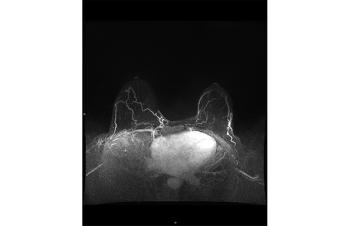

The value of GBCA in MRI images

Author(s)Ilana Cass, MD, Rola Saouaf, MD

These ten images can help ob/gyns recognize the additional information GBCA administration provides in MRIs.